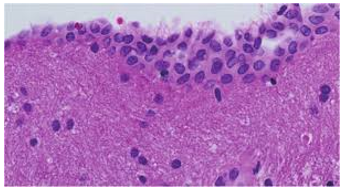

The Encephalic Wen- Neuro-Epithelial Cyst

Anubha Bajaj